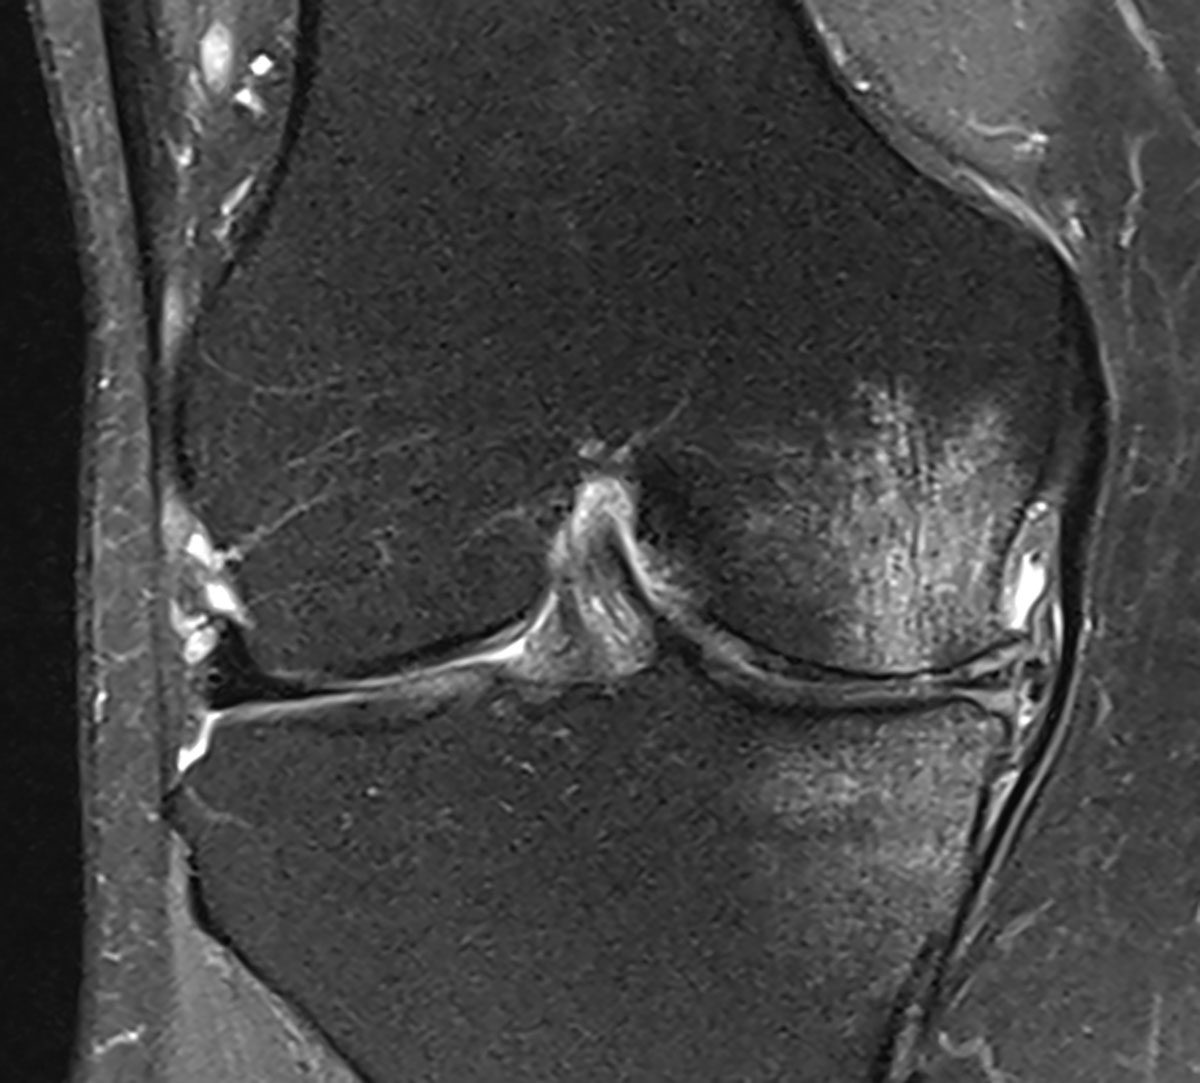

The active 64-year-old [female] patient, whom we had last treated at our practice in the spring of 2020, was already known to us. The patient has pronounced varus osteoarthritis that she developed a few years ago associated with Ahlback’s disease with considerable bone oedema at the time (Fig. 2). She reported that she had been symptom-free for almost two years since our last treatment, and that she could cope well with her everyday living including moderate sporting activities. Now she had once again been exposed to high physical demands while clearing the home of her aged mother, and this had reactivated her symptoms again. She had already had a follow-up MRI performed recently and asked us to quickly start a new course of treatment.

The recent MRI of the right knee joint (06/2022) shows considerably activated varus osteoarthritis, now with increased bone oedema compared with the previous images, effusion associated with irritation, and a small Baker’s cyst.